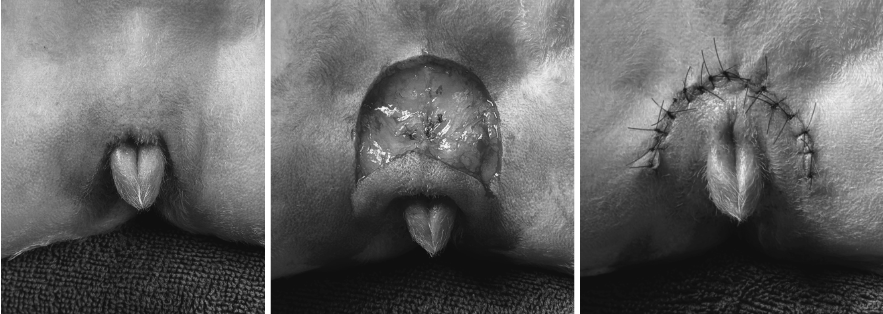

또한 강아지 환자는 함몰된 외음부로 인해 주변 피부염이 있었고, 이러한 구조적 문제는 세균이 역행해 방광까지 올라가 Struvite 결석 형성을 빠르게 유발할 수 있는 환경입니다.

따라서 본원에서는 방광결석 제거술과 함께 외음부 성형술을 동시 진행하기로 결정했습니다. 강아지 방광결석은 전통적으로 개복을 통해 제거하지만, 본원에서는 방광경을 삽입해 내시경으로 방광 내부를 관찰하며 결석을 하나씩 제거합니다. 커다란 결석들은 홀뮴 레이저를 이용하여 파쇄한 후결석을 제거합니다.

강아지 외음부 성형술 (함몰된 생식기를 피부 성형을 통해 주름을 제거) / 출처: 에스동물메디컬센터 양산점

외음부 성형술(함몰된 생식기의 주름을 제거해 구조를 바로잡는 수술)도 함께 진행하여, 결석 재발을 유발할 수 있는 해부학적 문제를 근본적으로 교정했습니다. 이를 통해 향후 재발 위험을 효과적으로 낮출 수 있는 기반을 마련했으며, 수술 직후 환자는 회복실에서 안정적으로 마취에서 깨어났습니다.